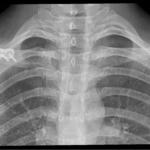

The initial assessment involves detailed history examination and review of previous x-rays. Specialized x-rays are usually required to complete the assessment. The initial assessment and discussion often takes an hour.